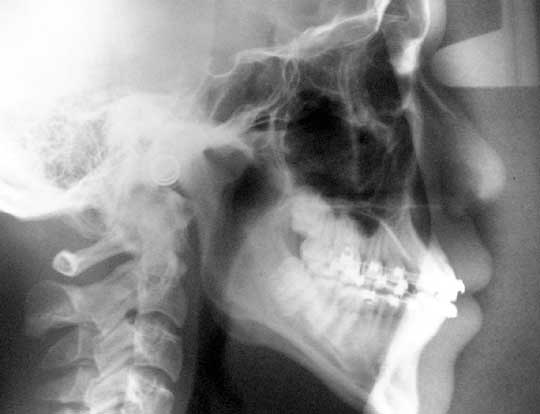

TEMPOROMANDIBULAR JOINT DISORDER (TMD) – treatment of jaw, head and neck pains. | PERIODONTICS – State of the art treatment of inflamed gums & loose teeth. |